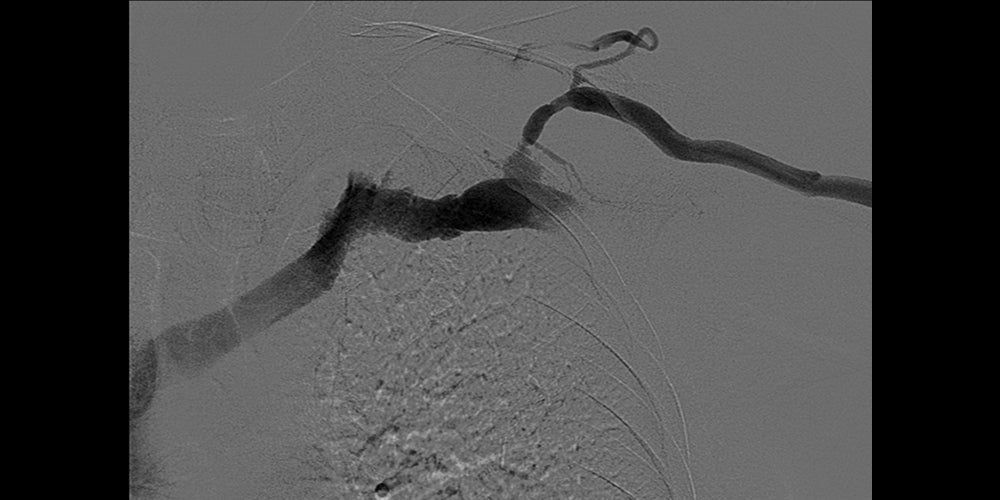

Direct left brachiocephalic fistula access. Venography demonstrated recurrent cephalic arch stenosis. Venoplasty to 7 mm with a high-pressure balloon and recoil stenosis. Upsizing of sheath access. Deployment of a 7 mm x 5 cm GORE® VIABAHN® Device, and post-dilatation.